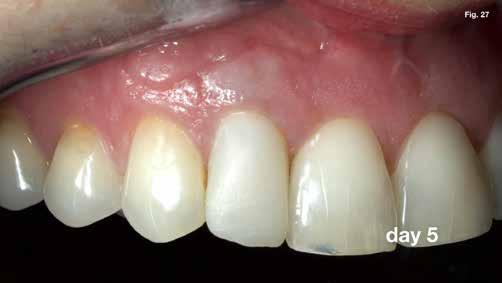

szárítottuk (18–20. ábra), majd retropecsétet (21–23. ábra) készítettünk „Neo Mta plus” (Avalon Biomed). A csontos blokkot visszahelyeztük (24. ábra) az eredeti helyzetébe, és a „Jason membrán” (Botiss Biomaterials GmbH) reszorbálható kollagénmembránt használtunk a blokkablak lefedésére (25. ábra). A lágyrészek varrására (26. ábra) nem felszívódó 6,0 monofilamentumos varratokat használtunk (SMI), amelyeket az 5. napon eltávolítottunk (27. ábra).

Eredmények: (3) és RAC-B összpontszám 2 (2-2-2/ 2) az 1 éves CBCT-követéskor (30–32. ábra), (4, 5,). Az 1 éves követéskor a lágyrészeken nem volt látható recesszió, csak enyhe színkülönbség a sebgyógyulás és a keratinizált szövet között, de ez a páciens számára nem aggályos (28. ábra).